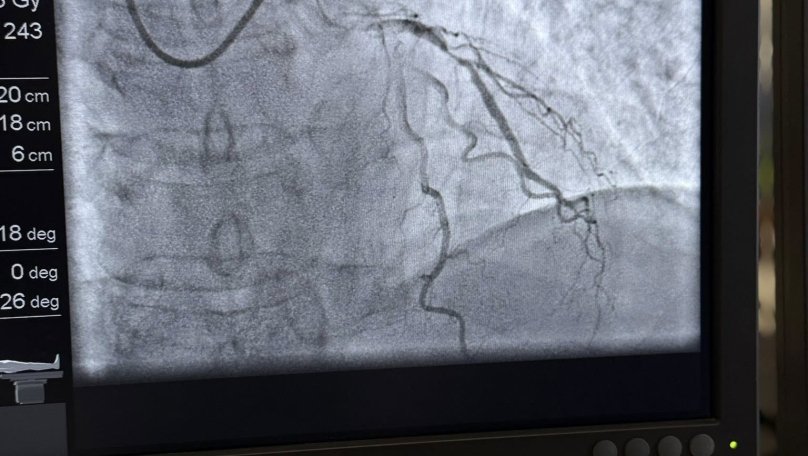

Лікарі виявили, що у пацієнта хронічний коронарний синдром — стан, при якому серце не отримує достатньо крові та кисню через звуження коронарних артерій. Після стабілізації стану пана Ігоря медики прийняли рішення провести операцію — стентування серцевих судин. З цього року така процедура стала безкоштовною для пацієнтів, як і ургентне лікування, завдяки Програмі медичних гарантій, яка покривається державним фінансуванням. Це означає, що саму операцію та необхідні матеріали, зокрема стенти, оплачує держава через Національну службу здоров’я України (НСЗУ).

«Під час операції я перебував у свідомості. Це не надто складне втручання, але дуже приємно, що воно безкоштовне. І зараз я почуваюся значно краще, ніж кілька днів тому», — розповів пан Ігор.